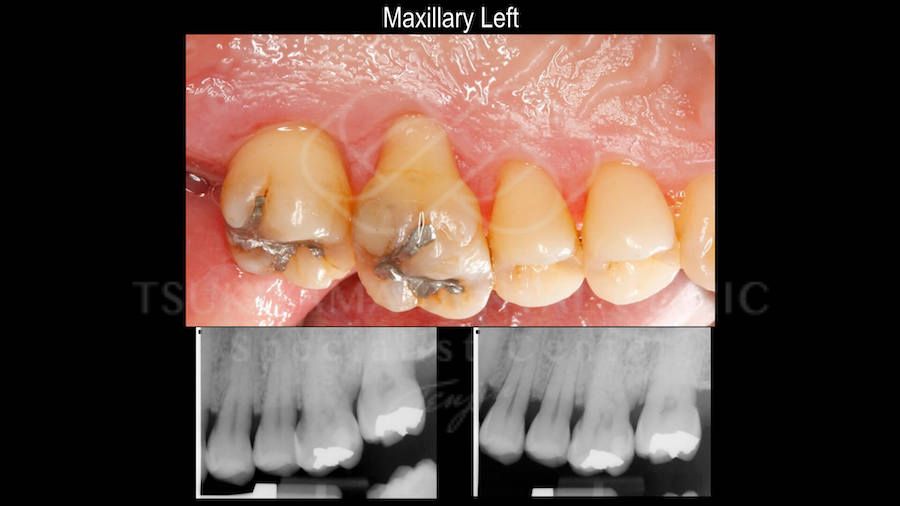

この処置は歯の周りの歯ぐきがとても薄くて歯磨きをする時に違和感が強かったり、矯正治療を行う際に歯が移動する方向の歯ぐきを強化するために行う歯ぐきの移植手術です。

上あごの健康で丈夫な歯ぐきを利用して移植を行います。

上あごの歯ぐきの色がそのまま移るため移植後の色は少し差がありますが、とても健康で丈夫な歯ぐきを獲得することが可能です。

術前と術後の比較